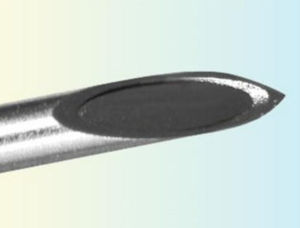

... 用于经皮提取细胞学和组织学样本的千叶针。 ...

... 用于经皮提取细胞学和组织学样本的带脊柱尖端的针头。 ...

... 用于经皮提取细胞学和组织学样本的 Franseen 针。 ...

... 用于经皮提取细胞学和组织学样本的格林式针头。 ...